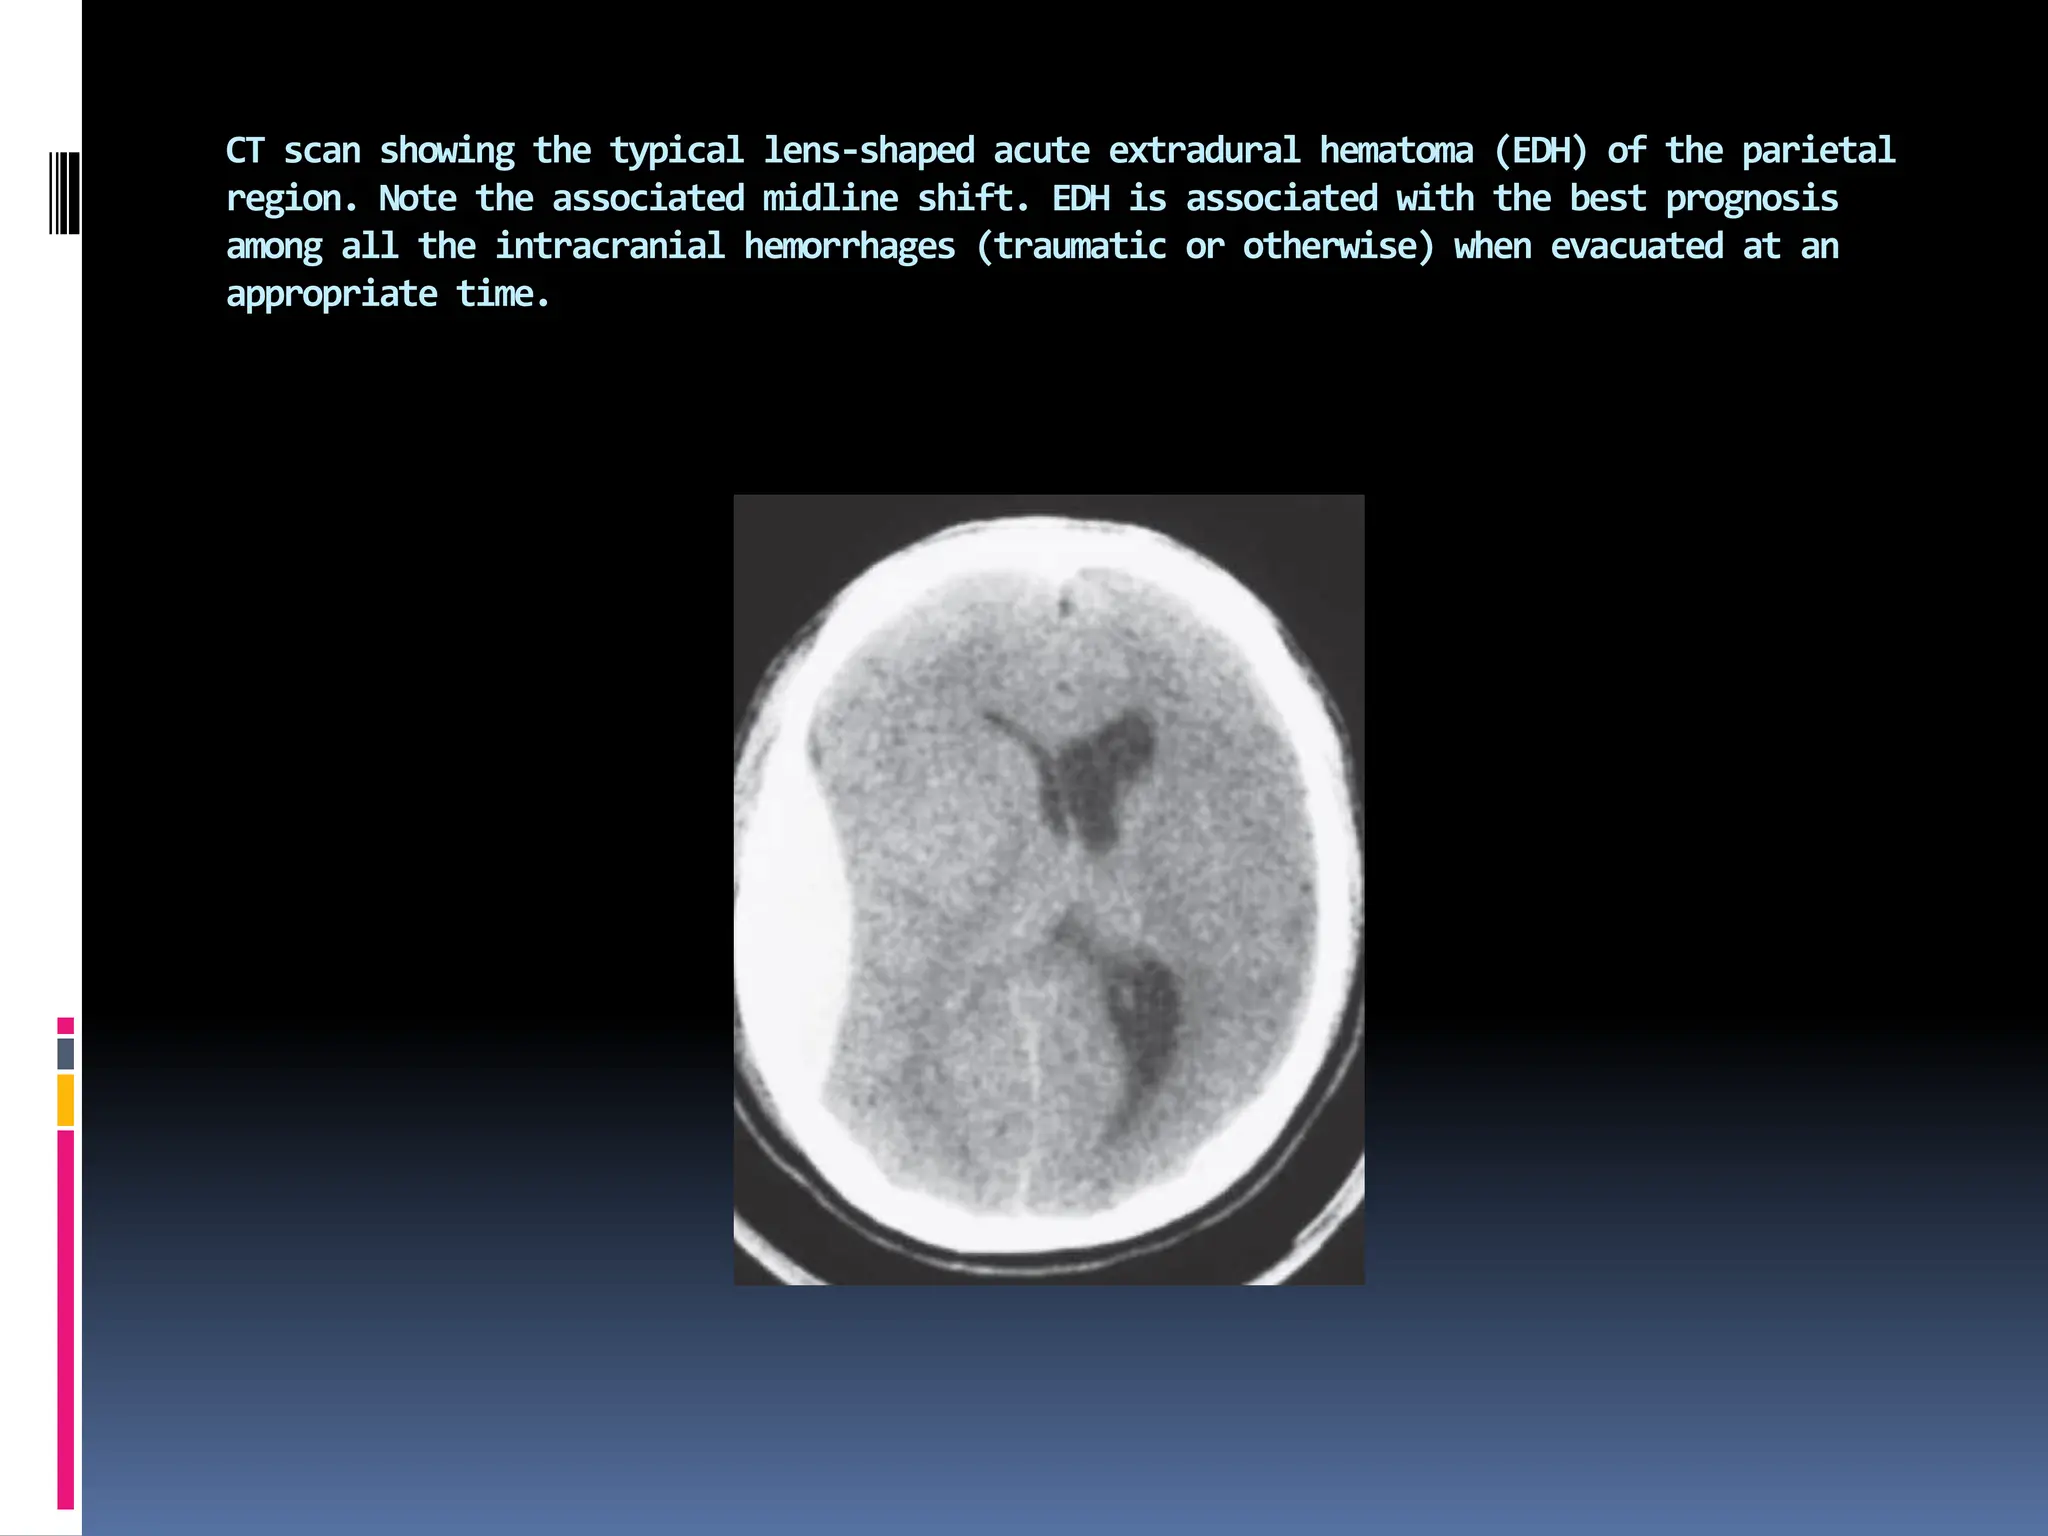

CT scan showing the typical lens-shaped acute extradural hematoma (EDH) of the parietal

region. Note the associated midline shift. EDH is associated with the best prognosis

among all the intracranial hemorrhages (traumatic or otherwise) when evacuated at an

appropriate time.